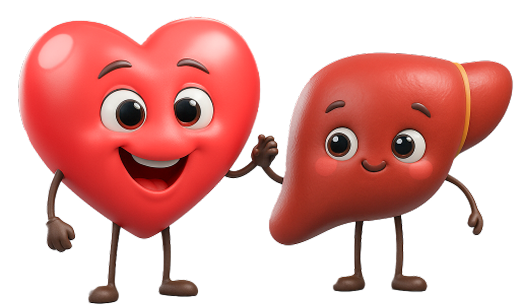

Тиазолин улучшает работу сердца и печени

противоишемическое действие

противоишемическое действие

мембраностабилизирующее действие

мембраностабилизирующее действие

антиоксидантное действие

антиоксидантное действие

иммуномодулирующее действие

иммуномодулирующее действие

защищает клетки организма от «агрессивных» молекул (свободных радикалов)

защищает клетки организма от «агрессивных» молекул (свободных радикалов)

восстанавливает активность «внутренних» антиоксидантов (ферментов супероксидисмутаза, каталаза, глутатионпероксидаза)

восстанавливает активность «внутренних» антиоксидантов (ферментов супероксидисмутаза, каталаза, глутатионпероксидаза)

улучшает получение энергии клеткой, особенно в условиях недостатка кислорода

улучшает получение энергии клеткой, особенно в условиях недостатка кислорода

увеличивает энергетический резерв клетки (повышает накопление АТФ)

увеличивает энергетический резерв клетки (повышает накопление АТФ)

Поддерживает энергетический баланс клетки

Поддерживает энергетический баланс клетки

улучшает кровоснабжение органов и тканей

улучшает кровоснабжение органов и тканей

снижает риск тромбообразования

снижает риск тромбообразования

снижает вязкость крови, улучшает микроциркуляцию

снижает вязкость крови, улучшает микроциркуляцию

повышает сократительную функцию сердца

повышает сократительную функцию сердца

снижает риска нарушений ритма сердца

снижает риска нарушений ритма сердца

улучшает вегетативную регуляцию сердца

улучшает вегетативную регуляцию сердца

защищает клетки печени от повреждения и ускоряет их восстановление

защищает клетки печени от повреждения и ускоряет их восстановление

предотвращает разрушение и жировую инфильтрацию клеток печени

предотвращает разрушение и жировую инфильтрацию клеток печени

улучшает синтез и выделение желчи

улучшает синтез и выделение желчи

Действующее вещество

Тиазотная кислота содержит в своем составе Триазольное кольцо (–C₃N₃–) — стабилизирует электроны, участвует в захвате радикалов Сульфогруппа (–SH или –S–) — активно взаимодействует с перекисными соединениями, снижая их окислительный потенциал.

Тиазотная кислота содержит в своем составе Триазольное кольцо (–C₃N₃–) — стабилизирует электроны, участвует в захвате радикалов Сульфогруппа (–SH или –S–) — активно взаимодействует с перекисными соединениями, снижая их окислительный потенциал. Тиазотная кислота поддерживает энергетический баланс и улучшает метаболизм клеток.

Тиазотная кислота обладает антиоксидантным, мемраностабилизирующим, антиаритмическим действием, улучшает кровоснабжение и функцию клеток. Это позволяет защитить клетки, особенно клетки сердца и печени, от повреждений, вызванных неблагоприятными факторами и стрессом.

Таким образом, Тиазолин – это не просто лекарство, а умный помощник, который позволяет организму справиться с нагрузкой, восстановиться и чувствовать себя лучше.